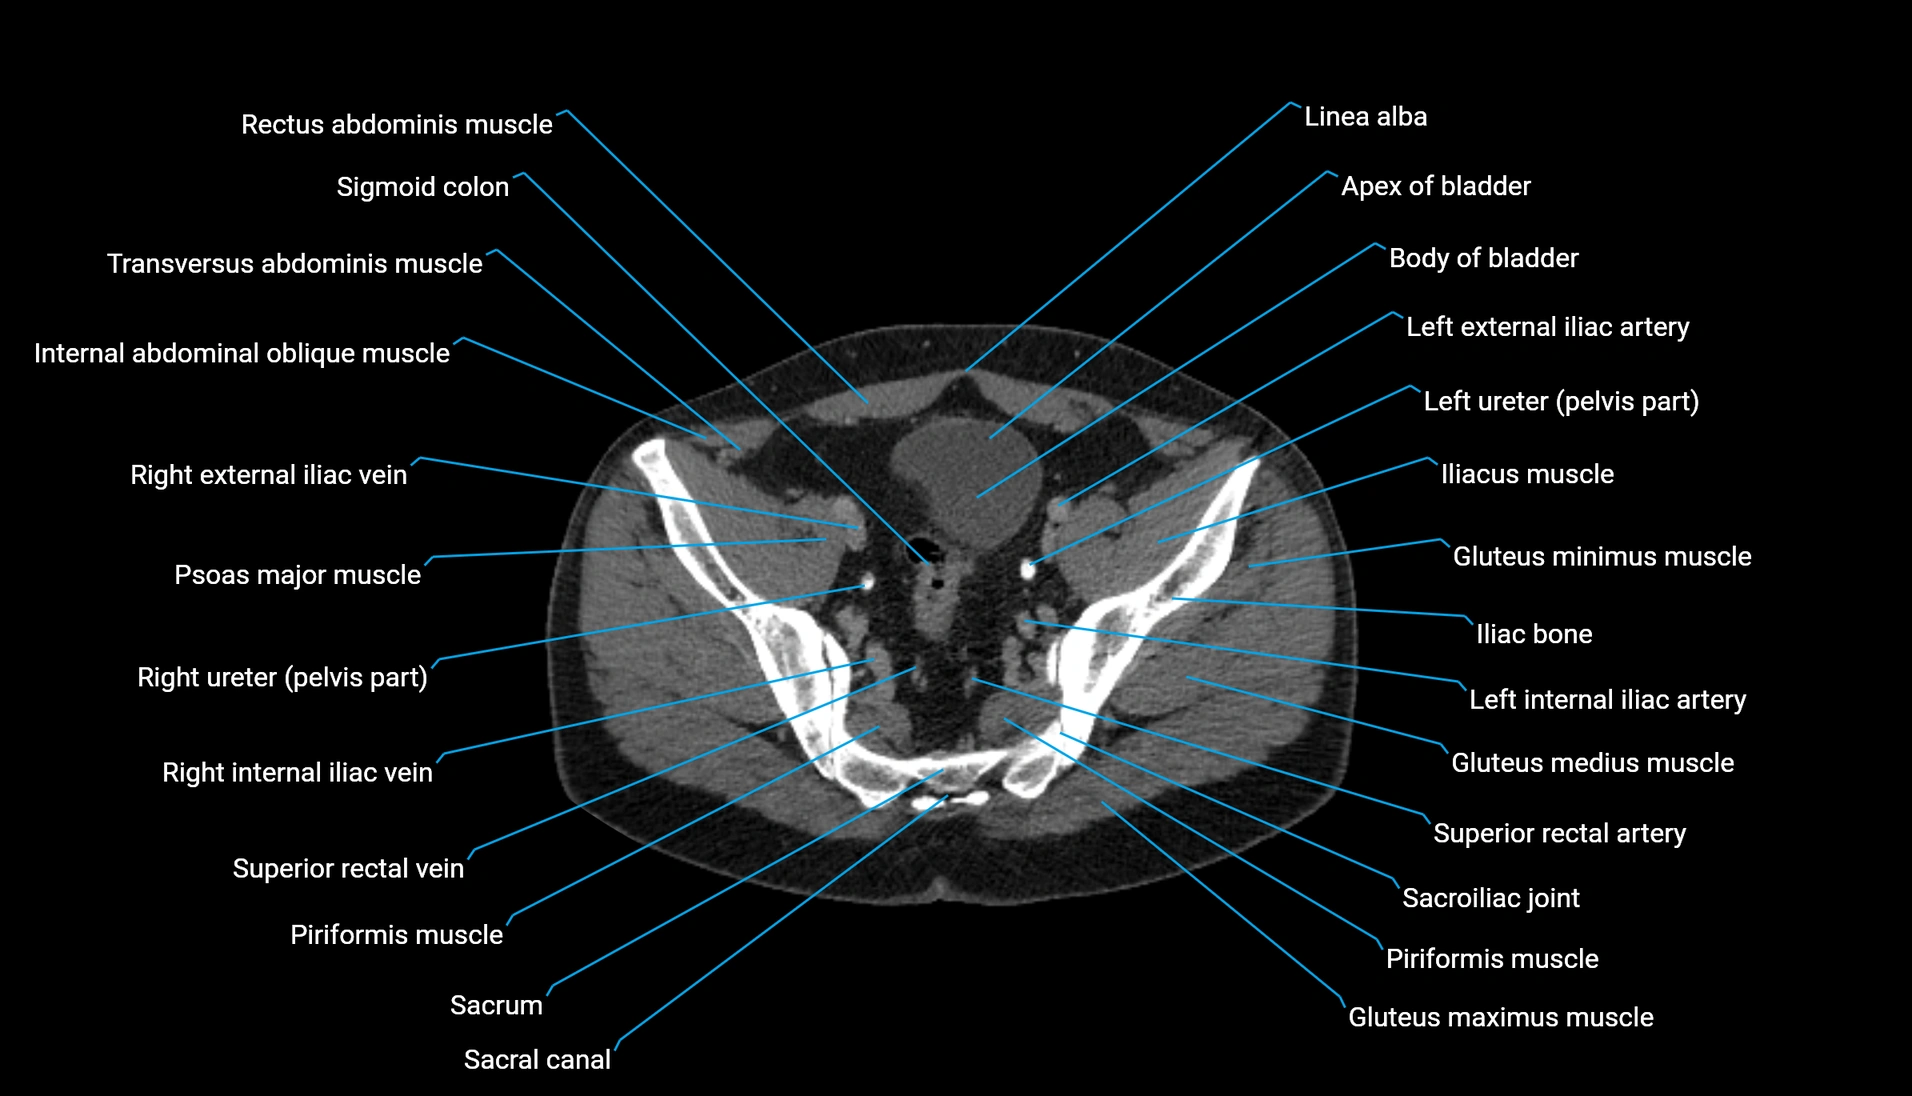

CT VRT 3D image

CT image